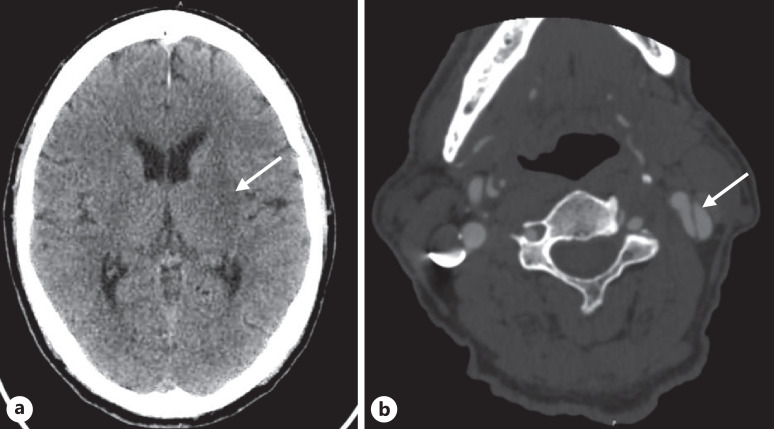

Case presentation: We report a patient with a chronic Stanford type A aortic dissection with dissection extension into the left common carotid artery and left internal carotid artery who had a good clinical outcome following mechanical thrombectomy for a symptomatic middle cerebral artery occlusion. We also review other cases in which endovascular mechanical thrombectomy was conducted in patients with aortic dissection and acute ischemic stroke and discuss the potential risks and benefits of carotid artery stenting in this clinical situation.